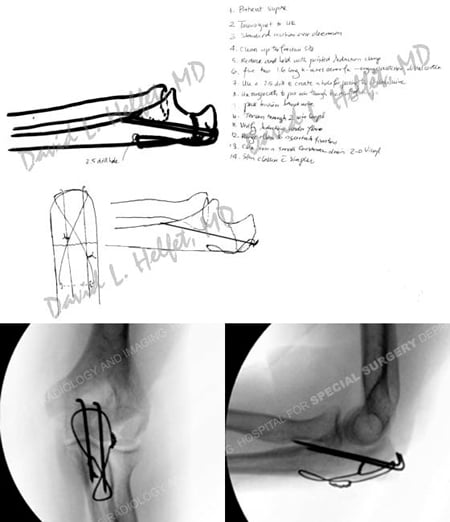

Pre-operative plan (top image) and intraoperative fluoroscopic radiographs (bottom images) following ORIF.